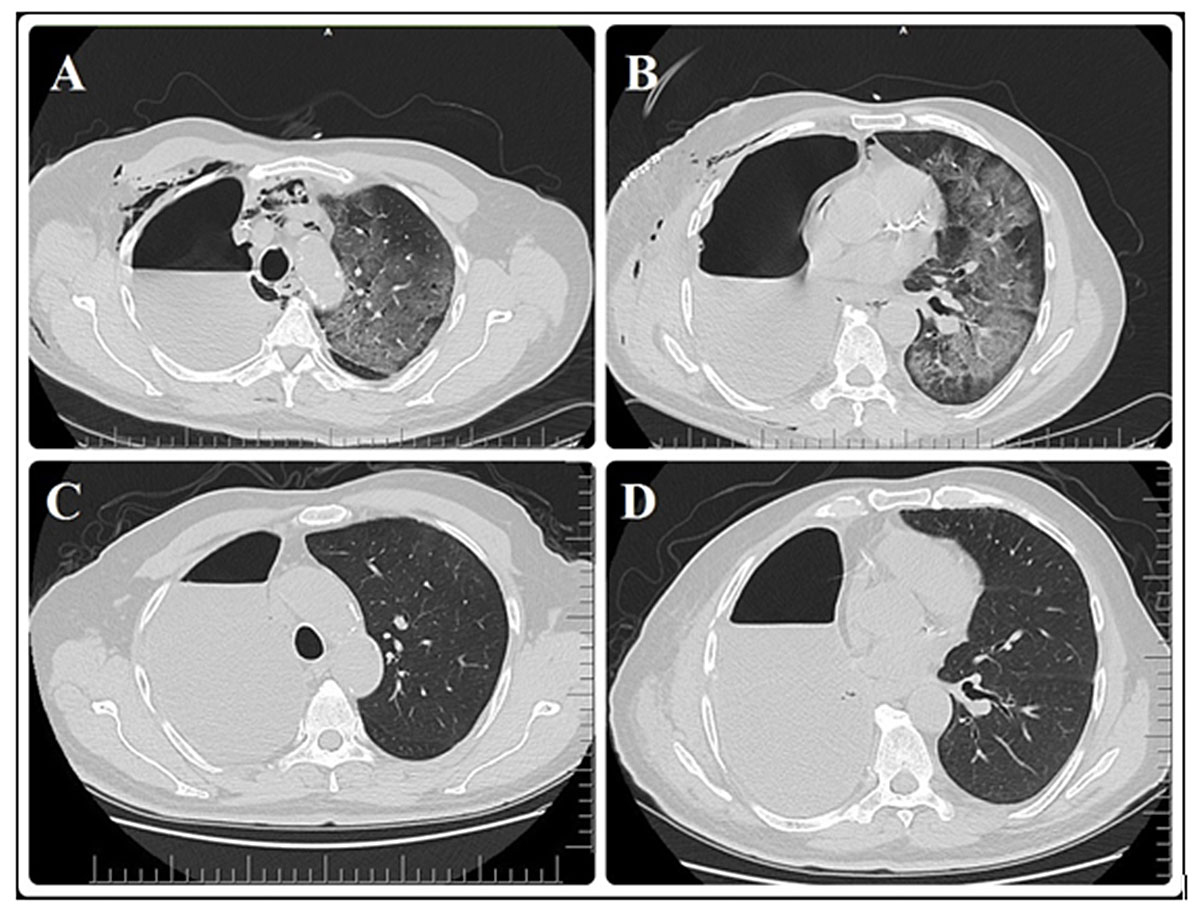

On postoperative day 4, the patient developed fever (38.7°C) and chills. Additionally, the dyspnoea worsened, and a dry cough, diffuse muscle pain and chest pain were present. Despite oxygen treatment with a high-flow nasal cannula, SpO2 was in the range of 70–80% and the heart rate was 110–120 beats/min. On chest x-ray, the non-homogeneous increase in density in almost all of the left lung was more evident. The WBC count and C-reactive protein (CRP) concentration were high; lymphocyte count and procalcitonin values were low (table 2). High-resolution computed tomography (HRCT) detected alveolar opacity and diffuse ground glass opacity in all segments except the left lung apex (fig. 2A,B). Blood, urine and sputum were cultured to determine the aetiology of the fever. Empirically, meropenem 3 × 1 g intravenously and linezolid 2 × 600 mg intravenously were added to the treatment regimen. In addition, a pharyngeal swab test was performed as viral pneumonia was suspected, and the patient was transferred to the special isolation intensive care unit. Non-invasive mechanical ventilation (NIMV) was applied because of hypoxia on arterial blood gas analysis (table 2).

Figure 2 (A,B) Postoperative day 4, images of HRCT from different cross-sectional levels taken after fever. Alveolar opacity, vascular congestion and inter-septal thickening areas in diffuse ground glass density in both lobes of left lung. (C,D) Control HRCT images taken on discharge (17th) day. It was observed that the ground glass opacity in both lobes of the left lung has recovered almost completely.

As the results of the pharyngeal swab test taken on the 15th and 16th postoperative days were both negative, WBC and lymphocyte counts were normal, the CRP levels continued to regress, there was no important biochemical abnormality and no hypoxaemia (table 2), and there were no additional symptoms other than minimal dyspnoea with effort, the patient was taken to the isolated normal service room. Since the almost complete recovery seen in a chest x-ray (fig. 1D) was confirmed by HRCT (fig. 2C,D), and no additional complications related to the surgery (bronchopleural fistula, haemorrhage, arrhythmia etc.) developed, a home-based treatment plan was created and the patient was discharged on the 17th postoperative day.

The radiological feature of lung lesions in COVID-19 pneumonia is ground glass opacity (GGO), which is an indicator of the early exudative phase [16]. In the case of a progressive disease, consolidation may develop in addition to GGO owing to intra-alveolar organisation. However, it has been shown in CT images following treatment that GGOs and consolidations can be largely cleared from both lungs [6]. Similarly, it was found that the diffuse GGO and consolidations that occurred over time in almost all of the left lung of our patient at postoperative day 4 were almost completely resolved after a successful 13-day period of treatment (figs 1D and 2B,C). In addition, it is known that there may be abnormalities on chest radiology in patients before the onset of symptoms in COVID-19 pneumonia [17]. The reason for the appearance of non-homogeneous opacities on the chest x-ray of our patient – who was radiologically evaluated 1 week earlier – since the postoperative day 1 is an indication that the patient was operated on when he had lung lesions. Therefore, during the pandemic even asymptomatic patients should be evaluated with at least one chest x-ray before surgery as this may be useful in terms of reducing the possibility of neglect. Also, it is important to consider an appropriate serology test and tomographic examination in order to investigate any lung infiltration, to know that radiological changes may occur before the symptoms and to exclude potential COVID-19 infection [16].